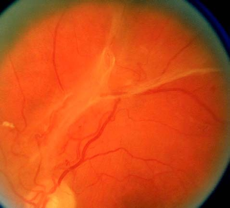

视网膜脱离

视网膜脱离是一种常见的糖尿病视网膜病变晚期严重并发症,可对患者造成显著的视力损伤。

糖尿病视网膜病变引起的视网膜脱离总是伴随“纤维-血管组织”的牵引。

在患者身体情况允许的情况下,应进行手术治疗。

▲ 视网膜脱离

▲ 视网膜前出血(PRH)可见于视网膜脱离的表面。